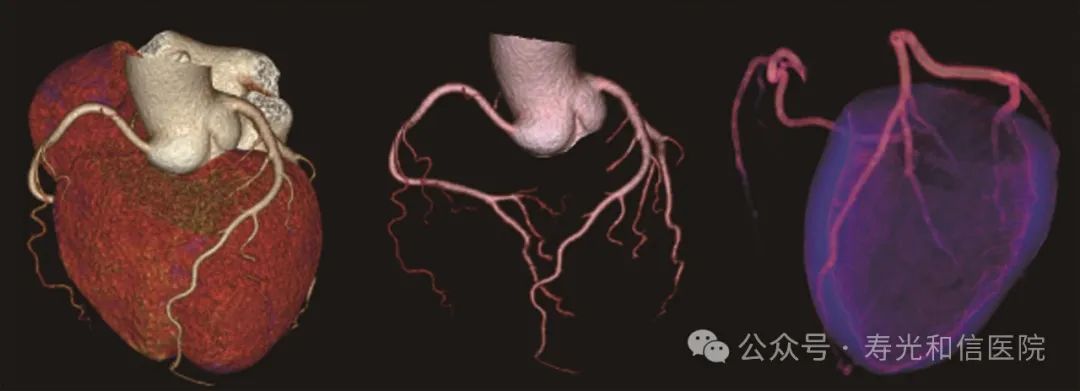

无限制心脏成像

凭借先进硬件平台和独有的AI冠脉追焦技术,不管是对于严重心律不齐、房颤、房扑,还是超高心率等一般CT做不了的心脏检查的情况,联影640层CT都可以获得高清的成像效果,助力精准临床诊断。